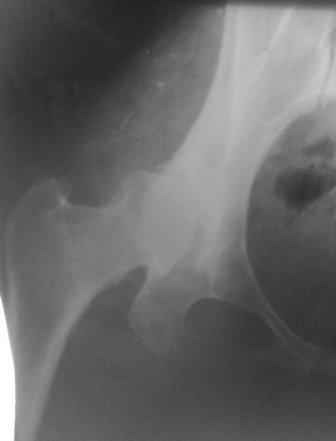

При определении показаний к м/в остеотомии учитываем не только функциональное состояние, но анатомическую форму сустава. Например, при той форме, что на картинке в вашем письме (мелкая впадина,уже не сферичная головка)НИИТО вполне обосновано предлагает ТЭП. Варизирующая остеотомия в "чистом виде" усилит конфликт в опорной зоне сустава. Если очень "настоятельно просит" - экстензия с наружной ротацией по R.Bombelli. То есть на открытом суставе бедро согнуть и ротировать внутрь до покрытия головки впадиной. Сформировать канал через шейку в головку с тем расчетом, что после м/в распила бедро нужно вывести в функциональное положение. Фиксировать 90 град. медиализирующей ортопедической пластиной с клинком. Но выздоровления не обещать, покрытие головки малое, длительного эффекта не будет. Нужна периацетабулярная остеотомия или пластика крыши, но это другая сложность и другая травматичность. Необходимость ТЭП оттянете лет на 10 в лучшем случае. Надо учитывать, что в этом случае ТЭП операция не первая, это увеличивает инфекц. риски и снижает функциональный результат для сустава. Я бы рекомендовал трость с противоположной стороны, ЛФК на приведение, чтобы подрос оссификат крыши и сформировались оссификаты головки. При нормотрофическом типе поражения можно будет провести вальгизирующую остеотомию, эффект которой более длительный или больная за это время найдет возможности приобретения ЭП.

Представляю Р-снимки: обзорная, с отведением и с приведением.

Глубокоуважаемый Абдурашид. Здесь нет снимка с отведением. Если Вы сами сходили в рентгенкабинет и лично отвели пораженную конечность максимально возможно, а также дали максимально возможную внутреннюю ротацию-это одно!!!! Значит у пациентки тяжелейшая приводящая контрактура тазобедренного сустава!! И необходимо разобраться-миогенная или артрогенная? Если же Вы просто назначили указанный снимок и доверили произвести укладку рентгентехнику-это другое!!! Одному богу известно, что она делала, ведь на р-снимке отведения нет!

Все предыдущие корреспонденты предлагают вам достаточно простую вещь-смоделировать предлагаемую Вами операцию (т.е. дать отведение и внутреннюю ротацию) и посмотреть, как изменятся соотношения в суставе. Не обижайтесь, но судя по представлению клинического случая угловые величины, характеризующие пространственные соотношения в тазобедренном суставе, ваши рентгенологи не считают.

Уважаемый Игорь Владимирович. диссертации М М Камоска, и В Е Баскова я нашел, но почему-то не могу открывать, и еще в данном случае имеется дисплазия т/б за счет недоразвития крыши в/впадины да и всей подвздошной кости, маргинального вывиха или латеропозиции головки вследствие лечебных ощибок нет, головка стоит на месте. Р-граммы сделал сам, но почему-то у больной отведение и внутренная ротация стали очень болезненной, и сухожилия приводящих мышц сильно натягивается.(контрактура артро-миогенная).

Глубокоуважаемый Игорь Владимирович! Признаюсь допустил ошибку, из-за напряженности работы и нехватки времени, когда повторно внимательно посмотрел все понял и не успел исправить ошибку до Вашего поста, конечно скошенность крыши в пределах 40гр,часть головки кнаружи линии Омбредана-Перкинса , облитерация дна вертлужной впадины и т.д.-это ДМВБ.